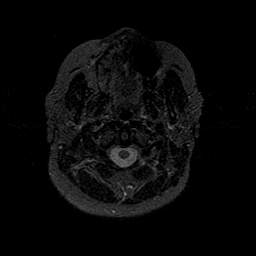

MR Study #1 -- Slice #3

[Home][Help][Clinical][Tour 1][Tour 2][Tour 3] Slice 3